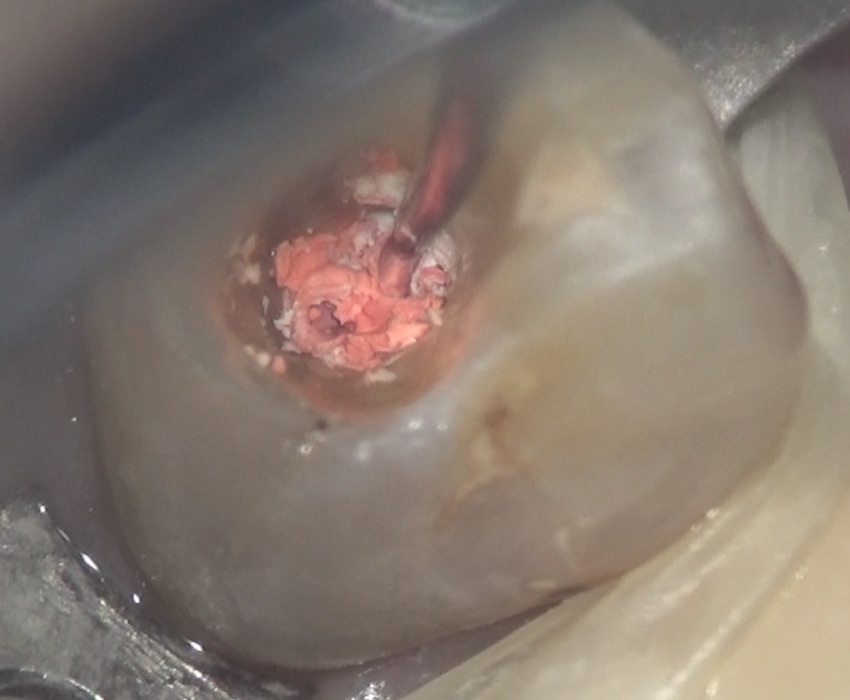

ラバーダムをして、マイクロスコープで内部を見ながら、

超音波チップで充填されていたガッタパーチャポイントと呼ばれる材料を取り除きます。

充填材を根管の内部から取り除いていると、こんなに汚いガッタパーチャが出てきました。